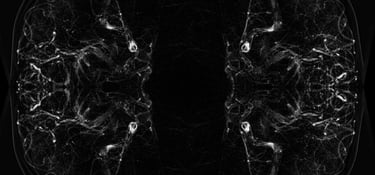

The audiovisual installation "Condition" is a portal that gives the viewer the opportunity to move into the world of the sick, which is full of pain, suffering and uncertainty, and to feel what the other feels and what this inner world looks like. The development of this topic was determined by the personal experience of the disease (multiple sclerosis). The diagnosis of the disease was unexpected for me, as for every patient. The experience of learning that your body is rejecting you and destroying everything from within is a shock. No one can even see this process, but you feel it, it is too difficult to talk about it, because there are no words to express it. This work is an expression of a personalized experience that allows us to see the inner world affected by the disease.